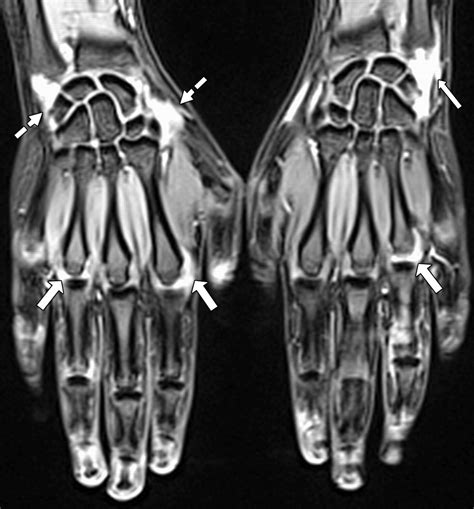

Common Findings in an MRI of Hand

An MRI of hand can reveal a variety of conditions and injuries. Some of the most common findings include:

• Fractures: Detailed images of bone fractures, including hairline fractures that may not be visible on X-rays.

• Tendon Injuries: Tears or inflammation in the tendons, which can cause pain and limited mobility.

• Ligament Injuries: Tears or sprains in the ligaments, which can affect joint stability.

• Arthritis: Signs of joint degeneration, inflammation, and bone spurs.

• Carpal Tunnel Syndrome: Compression of the median nerve in the wrist, causing numbness and tingling in the hand.

• Tumors and Cysts: Benign or malignant growths within the hand tissues.